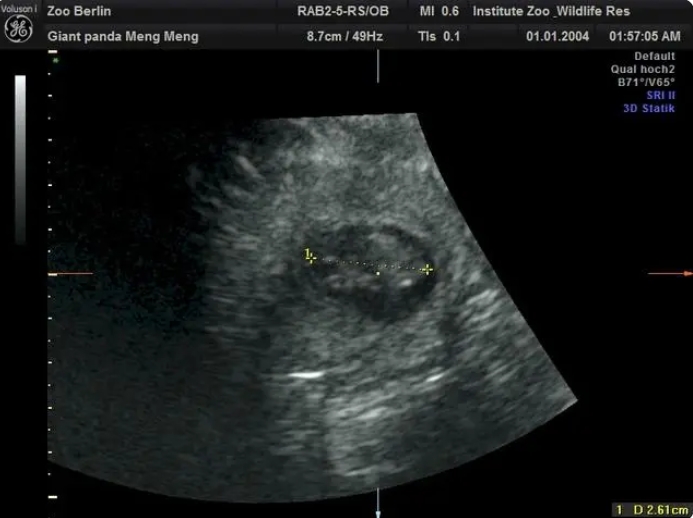

在園方11日上午進行的超聲檢查中,工作人員清楚地檢測到兩個熊貓?zhí)旱男奶?。目前兩個胎兒身長約2.5厘米。

柏林動物園介紹,根據(jù)目前胚胎的大小,如果一切順利的話,大熊貓雙胞胎預(yù)計將於8月底出生。